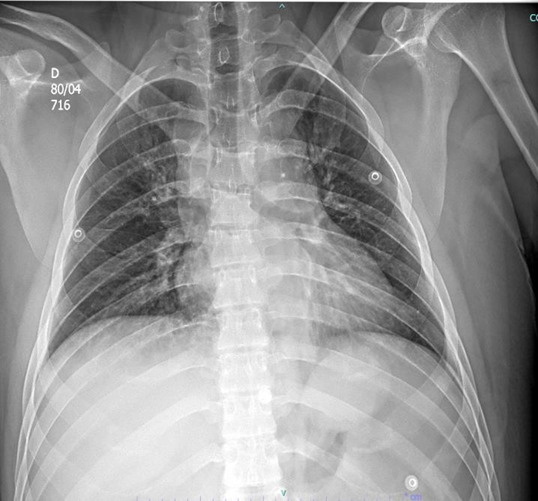

Figura 3: radiografia de fêmur direito.

Paciente do sexo masculino, 24 anos, da entrada no pronto-socorro do Conjunto Hospitalar de Sorocaba (CHS) dia 01/04/2025, vítima de colisão moto x anteparo fixo, apresentando fratura exposta de fêmur esquerdo, rotação externa de membro inferior direito com fratura exposta de fêmur direito distal e desalinhamento de antebraço esquerdo.

Frente ao caso, como conduta inicial foram solicitadas radiografias de tórax e pelve no leito, iniciada expansão volêmica com 500 mL de Ringer lactato (apresentando resposta com melhora da PA: 128×71 mmHg e FC 105 bpm), radiografia de fêmur bilateral, joelho bilateral, perna bilateral, braço e antebraço esquerdo, tomografias de crânio, face, coluna cervical, torácica e lombar, tórax, abdome e pelve, sendo as duas últimas com contraste. Além dos exames de imagem, foram solicitados também exames de laboratório.